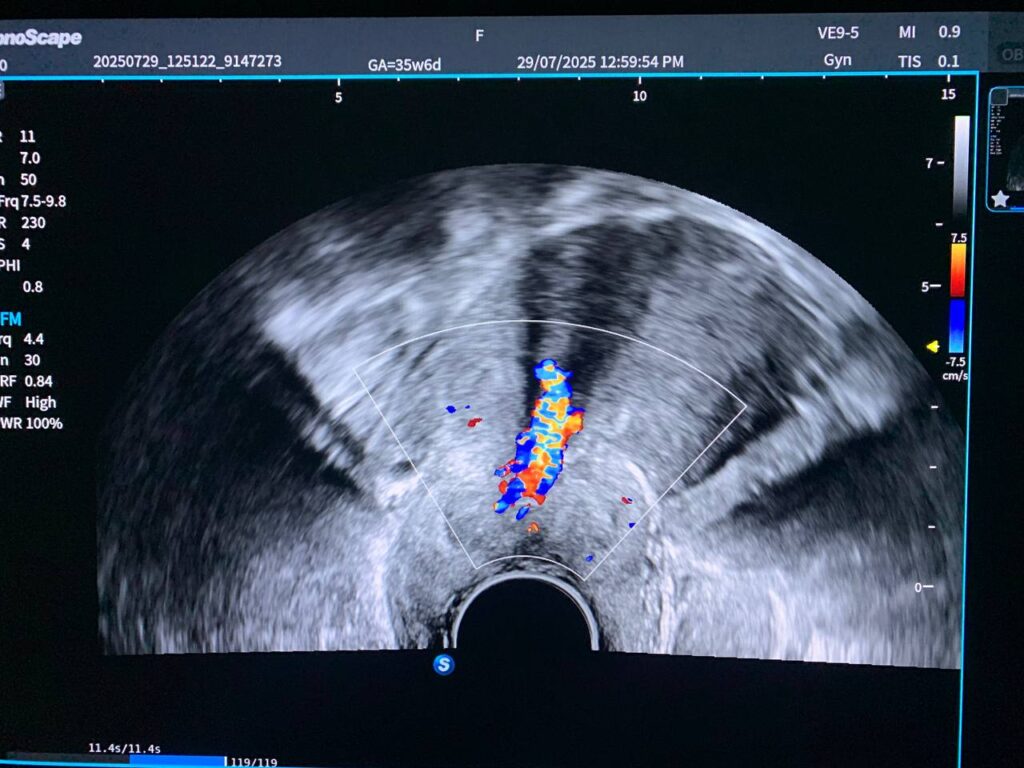

· Bulky uterus, endometrial lining thickness 6.2mm, with presence of isoechoic vascular solid mass within the cervical canal, its size >43x30mm, mostly pedunculated submucosal fibroid arise from posterior junctional zone , nearly at level of lower body